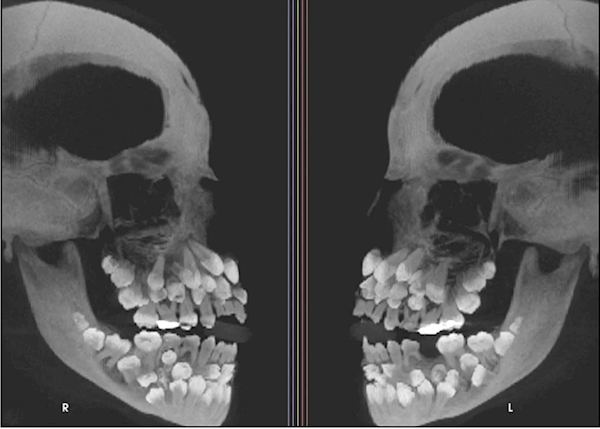

近日,巴西一名11岁女孩被发现口中竟有多达81颗牙齿(正常人拥有28-32颗恒牙),医学界为之震动。

据悉,该女孩来自米纳斯吉拉斯州,当天她前往牙科检查,打算拔除残留的乳牙,然而牙医通过X光检查发现她竟然满口都是牙!

经确认,女孩嘴里存在18颗乳牙和32颗恒牙,还额外长出了31颗“超生牙”,属极罕见的“多重超数牙”病例。

后医生通过CT扫描及染色体检测,发现其第9号染色体存在一处罕见变异,不过目前尚无法确认该变异是否直接导致牙齿异常。